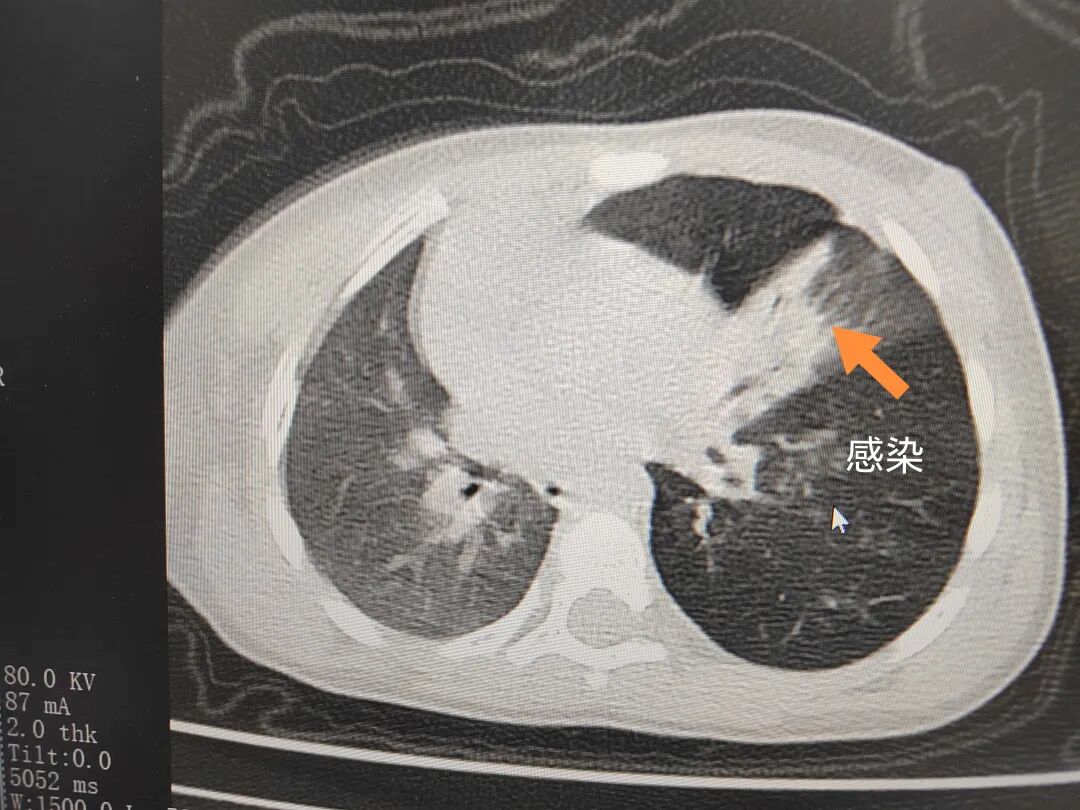

三天后(11月13日),趙寶出現(xiàn)高熱、咳喘加重,家長(zhǎng)著急了,再次帶他來(lái)到醫(yī)院。CT檢查顯示左肺過(guò)度充氣,左肺上下葉支氣管主干見(jiàn)不規(guī)則高密度影,左肺上葉可見(jiàn)大片狀密度增高影,縱隔窗實(shí)變,提示為“左側(cè)支氣管內(nèi)異物并繼發(fā)性改變,左肺上葉舌段肺膨脹不全”。

市二院小兒呼吸內(nèi)科副主任楊亞娟介紹,異物誤入氣道可能導(dǎo)致氣道阻塞,嚴(yán)重時(shí)可引發(fā)窒息,甚至危及生命。若異物進(jìn)入支氣管,造成不完全堵塞,可引起阻塞性肺氣腫;如完全堵塞支氣管,則可能導(dǎo)致肺組織萎縮,形成肺不張。此外,若異物存留時(shí)間較長(zhǎng),或?yàn)橹参镄援愇铮菀缀喜⒓?xì)菌感染,產(chǎn)生膿性分泌物,進(jìn)而發(fā)展為肺炎。她強(qiáng)調(diào),盡早診斷并取出異物,是減少并發(fā)癥、降低病死率的關(guān)鍵。